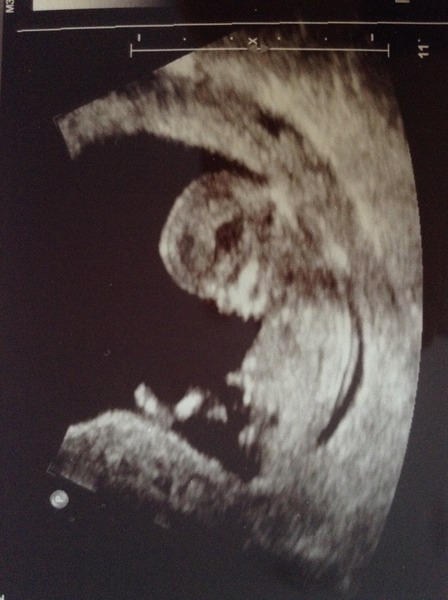

yaaay congratulations biffle and earlgrey .. Lovely scan pictures ...